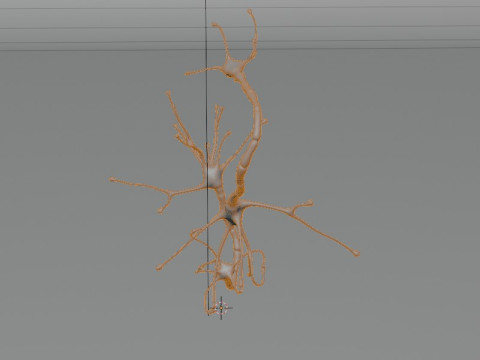

Neuron Sel Saraf Realistis Low-poly Model 3D

Neuron Sel Saraf Realistis Model 3D blend, png, Dari 3dcreations

A highly detailed and realistic 3D model of a human nerve cell (neuron), showcasing dendrites, axon, and synaptic terminals with scientific accuracy. Perfect for anatomy study, educational visualization, and medical simulations.

⚙️ Key Features:

Realistic and scientifically accurate nerve structure

Includes detailed axon, dendrites, and cell body

Ideal for educational and medical 3D projects

Smooth mesh topology for easy rendering and animation

Suitable for VR, AR, and scientific visualization

High-quality texture and proportionally accurate modeling